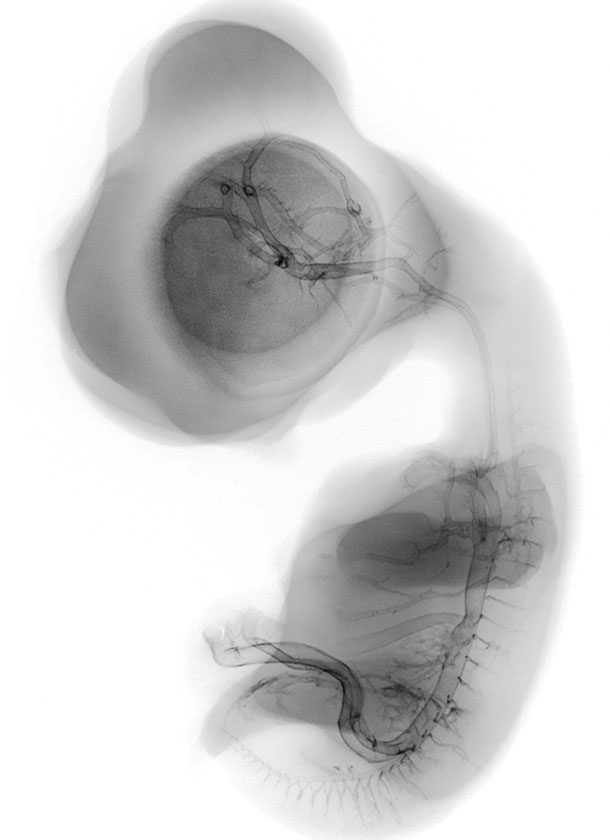

The Chick Embryo Microangiography website is a collection of micrographs depicting the vasculature of chick embryo development from day 2.5 to day 9. The chick typically hatches at day 21. Days 2.5 to 9, as represented in this collection, correspond to Hamburger-Hamilton (HH) stages 16 to 35. Hatching typically occurs at HH stage 46. The collection of images is intended to serve students, researchers, and the general public interested in viewing, studying and teaching animal development.

Composite Image of numerous chick embryo x-ray micrographs